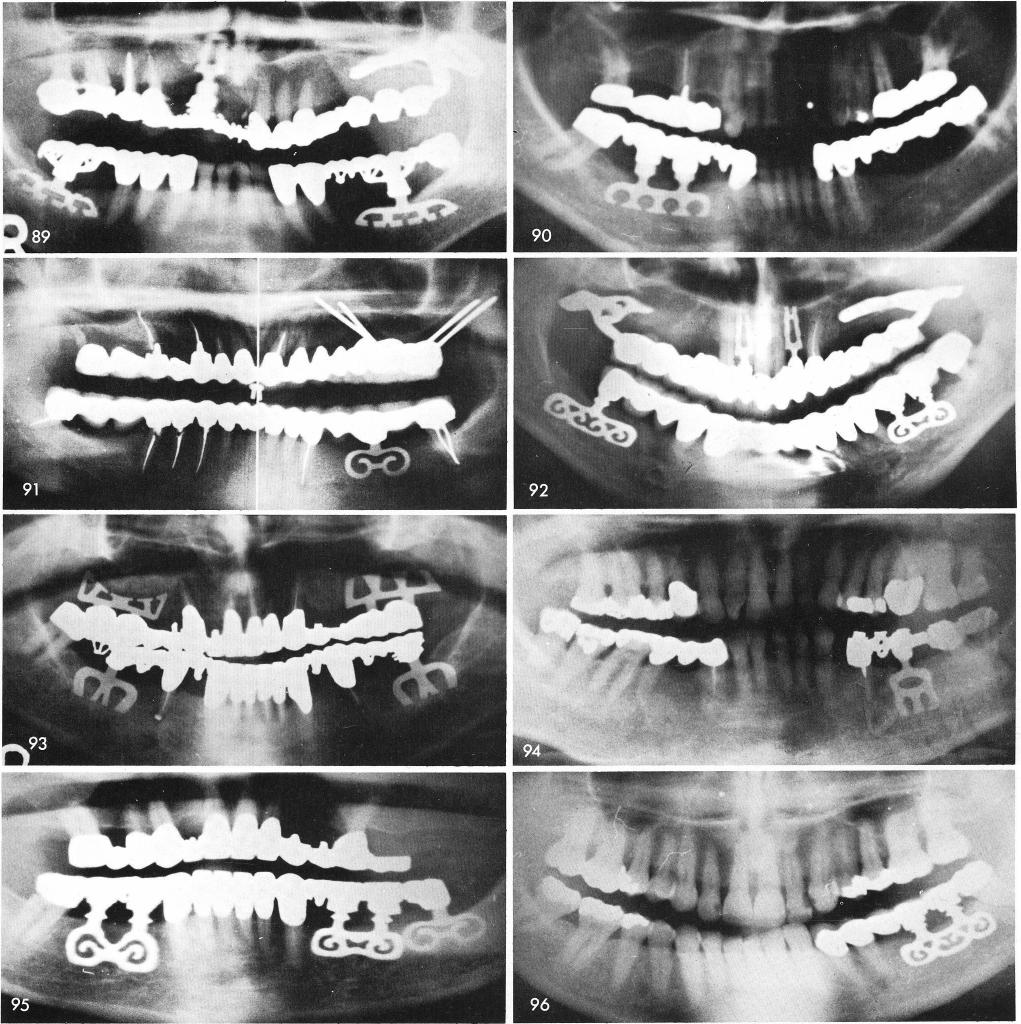

Mandibular Implants (published 1977)   Dr. Leonard I. Linkow